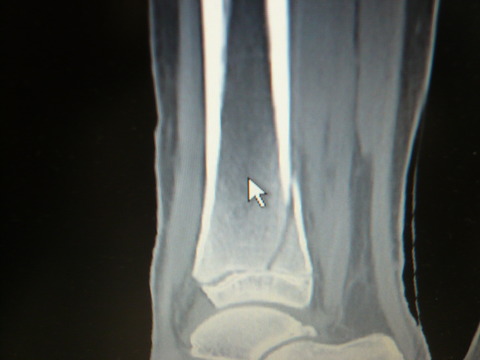

単純X線像では脛骨遠位骨端離解(Salter-Harris type 2)でした。私の経験症例は転位が10mm未満のことが多かったのですが、今回はめずらしく転位が大きかったです。

脛骨遠位骨端離解を完全に整復することは難しく、側面像で2-3mm程度の転位が残存するケースが多い印象です。この程度の転位はある程度許容せざるを得ないのかなと考えています。